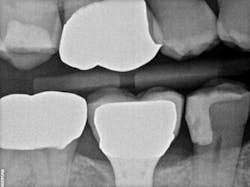

Recently, I changed my protocol for doing Class II dental restorations. I have started using indirect restorations more often. Depending on the size of the restoration, I now use indirect composites, inlays, onlays, and occasionally full-coverage crowns. Using indirect restorations allows one to control the emergence profile of the restoration and also ensures tight proximal and broad interproximal contacts. See Figures 3 through 6.

present at DL line angle not seen on radiograph.

food debris in the contact area.

embrasure space. Distal of No. 28 was restored as well;

not seen in this radiograph.